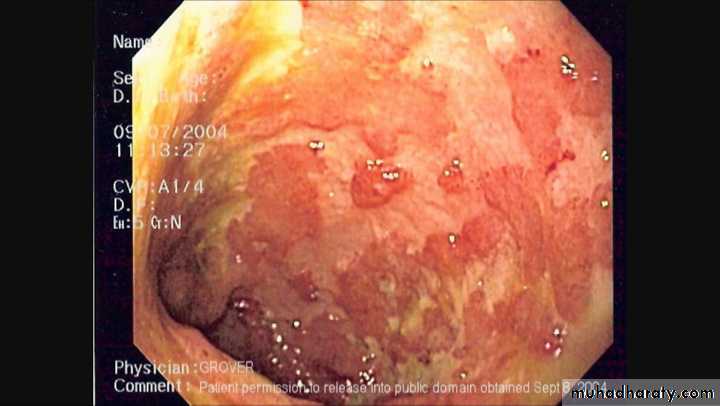

Colonic inflammation is diffuse,confluent and superficial, primarily affecting the mucosa and sub mucosa.Chronic mucosal ulceration is associated with formation of granulation tissue and regeneration ,leading to a polyp like pseudopolyposis,

Histological examination reveals inflammatory cells in lamina propria,walls of crypts,and there are crypt abscesses.There is depletion of goblet cell mucin .

Endoscopy and biopsy by sigmoidoscopy or colonoscopy.